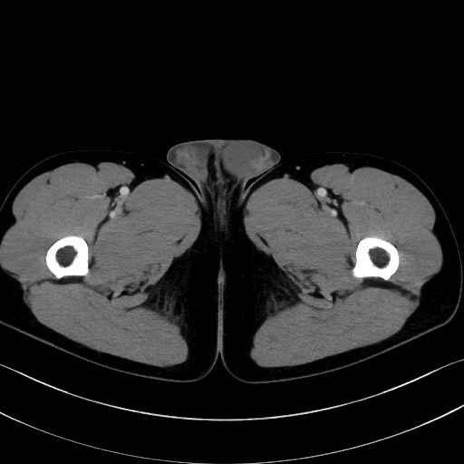

内閉鎖筋(obturator internus) のCT画像の解剖

内閉鎖筋 (Obturator internus)